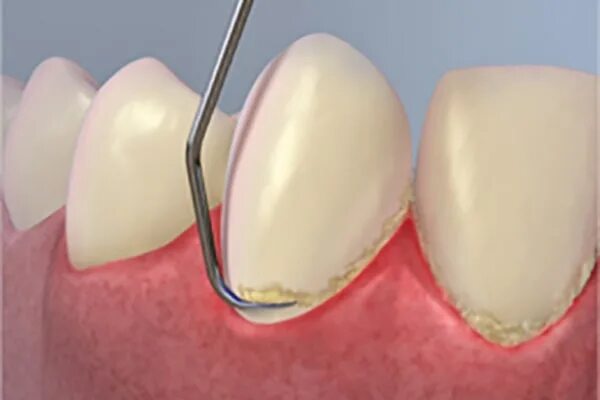

Зубной карман